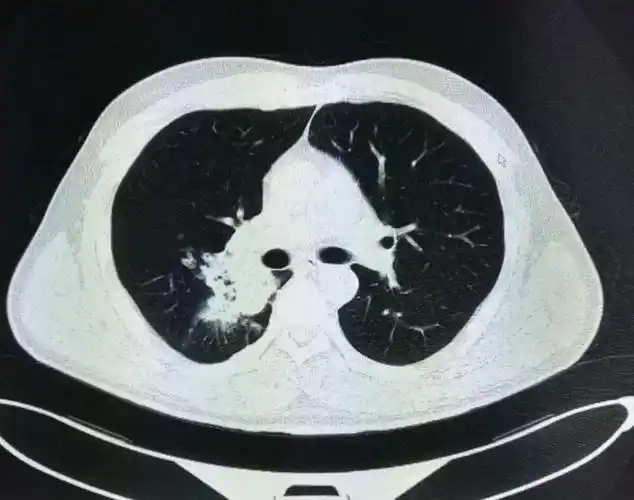

右侧中心型肺癌,右肺切除术后两年,术后残腔?——中心医院病例库